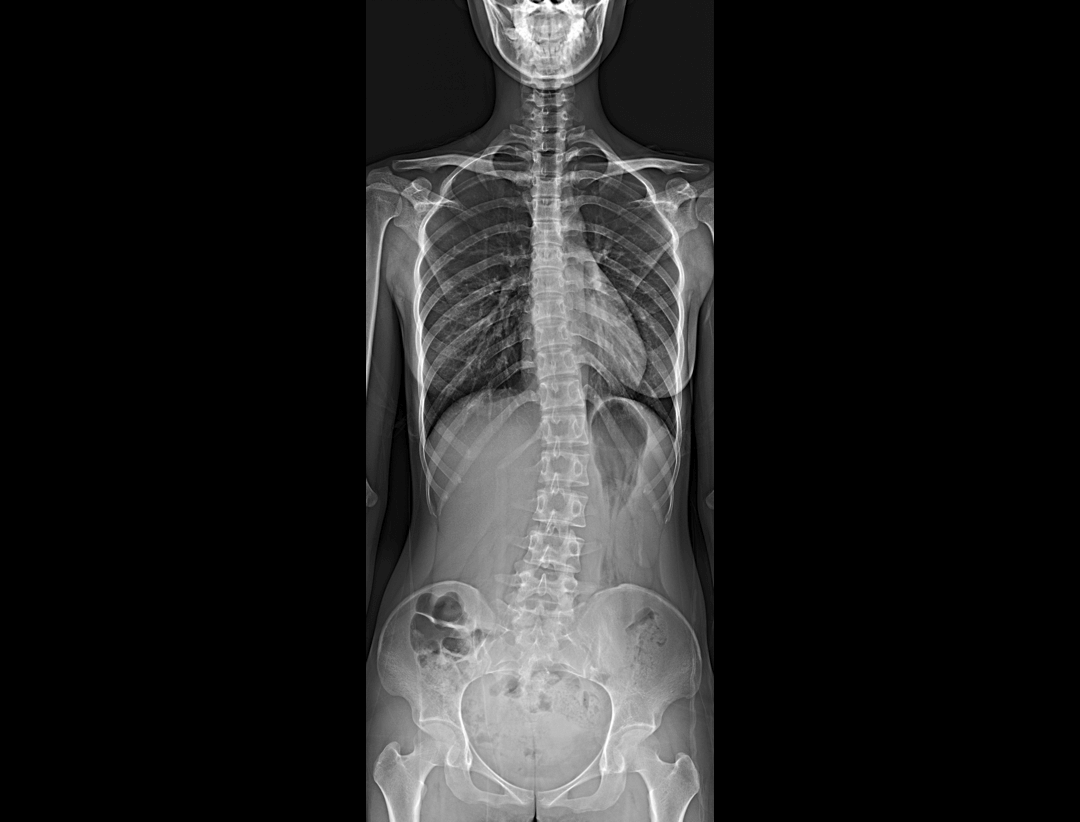

全自动无尺全景拼接*

支持自动立位无尺全景拼接,为骨科、整形外科提供高质量全景影像。

集成脊柱Cobb角及股骨颈干角测量功能,精准指导外科手术及术后评估。